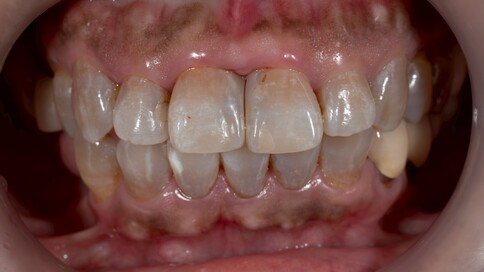

✨ 一、 單顆修復的極致挑戰

當您只有「單顆」門牙受損時,挑戰在於模仿隔壁那顆「天生的牙」。我們利用全瓷冠的高透光性創造視覺平衡,避免做出一顆看起來很新卻很突兀的假牙。

Case 1:舊假牙死白換新,牙肉回彈跡象。